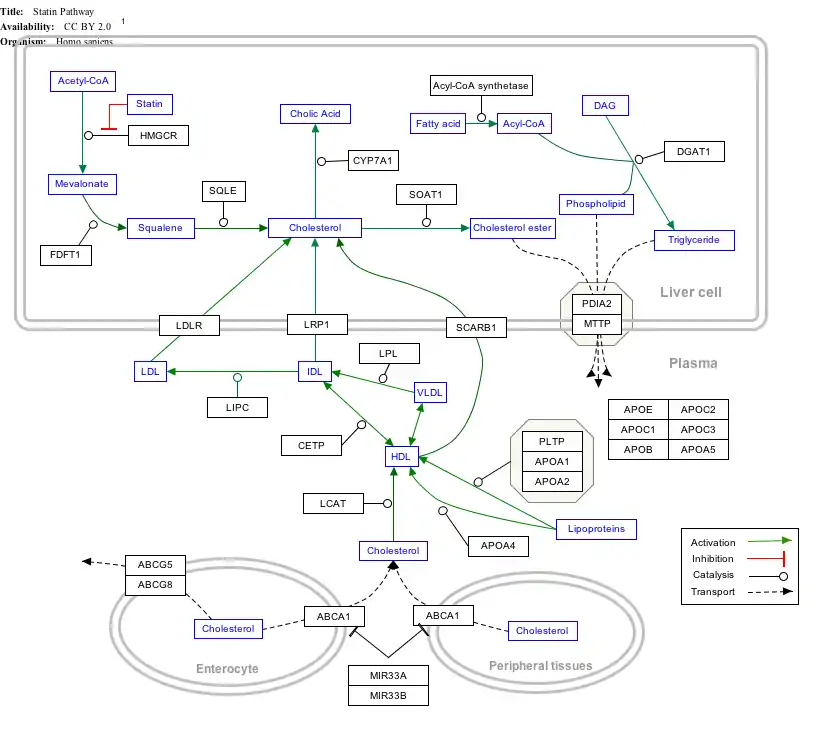

Interactive pathway map

Click on genes, proteins and metabolites below to link to respective articles. [§ 1]

- ↑ The interactive pathway map can be edited at WikiPathways: "Statin_Pathway_WP430".